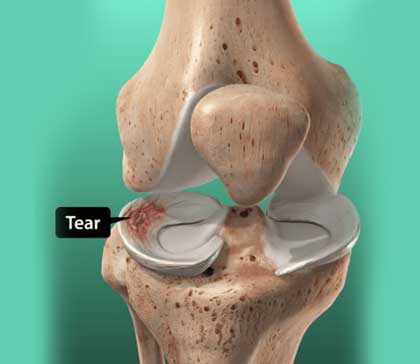

Meniscus surgery is an operation to remove or repair a torn meniscus, a piece of cartilage in the knee.

Each knee has two menisci. They are rubbery, C-shaped cushions that serve as shock absorbers in the knee joint. If your meniscus is injured or torn (often called torn cartilage), your healthcare provider may recommend surgery to remove the damaged part or repair it.